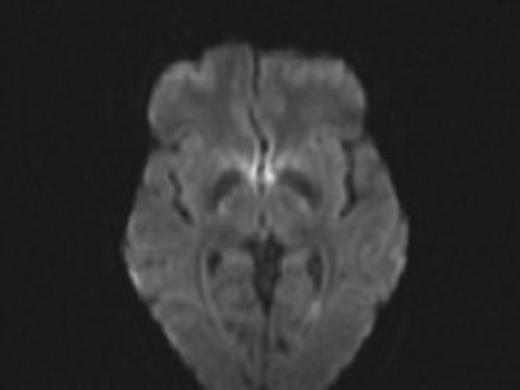

We report the case of a 34-year-old woman with a history of pilocytic astrocytoma resection and radiotherapy with ventriculoperitoneal shunt placement as a child who presented with altered mental status and nausea. She was found to have acute hydrocephalus without any pathology noted on MRI (Fig. 1). She was found to have a shunt fracture at the level of the neck and was taken to the operating room for shunt revision (Fig. 2). At this time, she had an entirely new shunt placed including a programmable valve with an anti siphon device. Post-operatively she did well and was discharged home.

Difussion MRI of the brain prior to syndrome showing no areas of stroke.